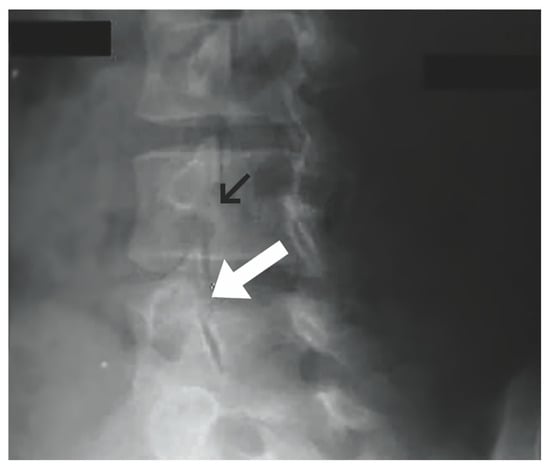

1.9.1. Buck’s Repair

- Buck, J.E. Direct repair of the defect in spondylolisthesis. J. Bone Jt. Surg. Br. Vol. 1970, 52-B, 432–437. [Google Scholar] [CrossRef]

- Li, Y.; Li, H.; Chang, X.; Hu, Z.; Mu, X.; Liu, C.; Gao, X.; Zhang, Y.; Zhou, Y.; Li, C. Retrospective comparative study of pedicle screw fixation via quadrant retractor and buck’s technique in the treatment of adolescent spondylolysis. Orthop. Surg. 2022, 14, 111–118. [Google Scholar] [CrossRef] [PubMed]

- Bonnici, A.V.; Koka, S.R.; Richards, D.J. Results of Buck screw fusion in grade I spondylolisthesis. J. R. Soc. Med. 1991, 84, 270–273. [Google Scholar] [CrossRef]

- Snyder, L.A.; Shufflebarger, H.; O’Brien, M.F.; Thind, H.; Theodore, N.; Kakarla, U.K. Spondylolysis outcomes in adolescents after direct screw repair of the pars interarticularis. J. Neurosurg. Spine 2014, 21, 329–333. [Google Scholar] [CrossRef]